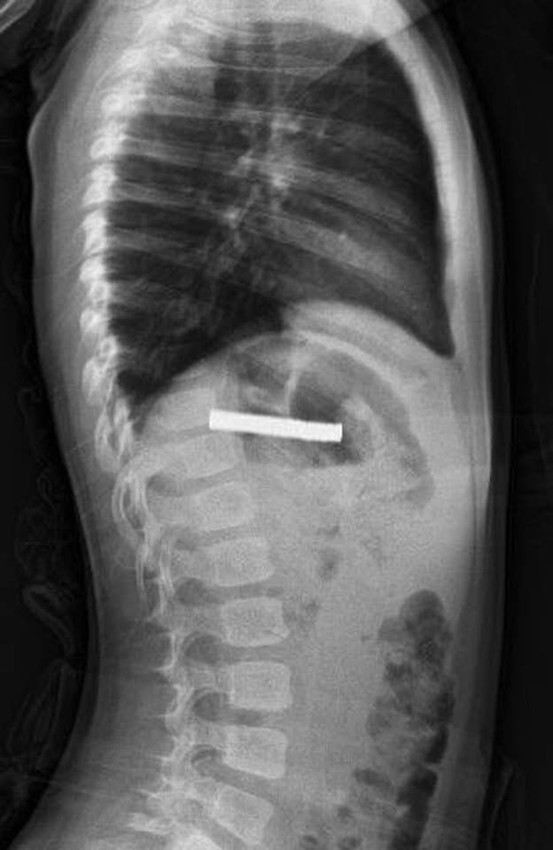

Elazığ’da 3 yaşındaki bir çocuğun yuttuğu 19 mıknatıs, Fırat Üniversitesi Hastanesinde başarılı bir operasyon ile çıkartıldı.

Edinilen bilgiye göre, Erzurum’da bir çocuk evde bulunan 19 tane mıknatısı yuttu.

Çocuğun rahatsızlanması sonucu durumu öğrenen aile hastaneye başvurdu.

Daha sonra çocuk Elazığ’a sevk edildi. Fırat Üniversitesi Çocuk Gastroenteroloji Hepatoloji ve Beslenme Bilim Dalı Başkanı Prof. Dr. Yaşar Doğan, çocuk hastanın yemek borusuna yapışmış 19 mıknatısı endoskopik yöntemle çıkardı.

Mıknatıslar uzun süre yemek borusunda takılı kaldığı için yemek borusu ve mide girişinde zedelenmeler olurken, çocuğun sağlık durumunun iyi olduğu ve taburcu edildiği öğrenildi.